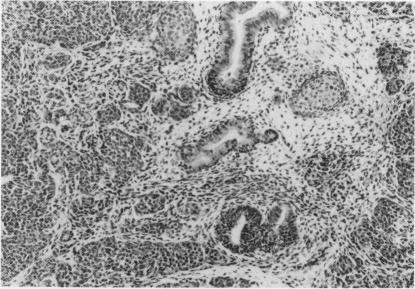

Murine embryonal carcinoma cells, the pluripotent stem cells of teratocarcinoma were injected simultaneously into caudal and cranial sites on the back of syngeneic recipients in order to determine whether regional anatomical differences affect their take and growth rate and differentiation. The overall tumour take rate was higher in caudal than cranial sites, but the initial weight of tumours was higher in the cranial than caudal sites. Tumours developing in the two anatomical sites grew at the same rate with a linear increase in volume. At the end of the 4-week experimental period the differences in the size of anterior and posterior tumours were negligible and no histological differences were noted between the two groups. Our data indicate that regional factors significantly affect the take rate and the initial growth of this murine teratocarcinoma, i.e. the establishment of solid tumours from injected stem cells. The growth rate of established tumours was not affected by regional factors.

为了确定区域解剖差异是否会影响其植入率、生长速度和分化情况,将小鼠胚胎癌细胞(一种畸胎癌的多能干细胞)同时注射到同基因受体背部的尾部和头部位置。总体而言,尾部的肿瘤植入率高于头部,但肿瘤的初始重量在头部高于尾部。在两个解剖部位生长的肿瘤生长速度相同,体积呈线性增加。在为期4周的实验期结束时,前后肿瘤大小的差异可以忽略不计,两组之间未观察到组织学差异。我们的数据表明,区域因素显著影响这种小鼠畸胎癌的植入率和初始生长,即从注射的干细胞形成实体瘤。已形成肿瘤的生长速度不受区域因素的影响。